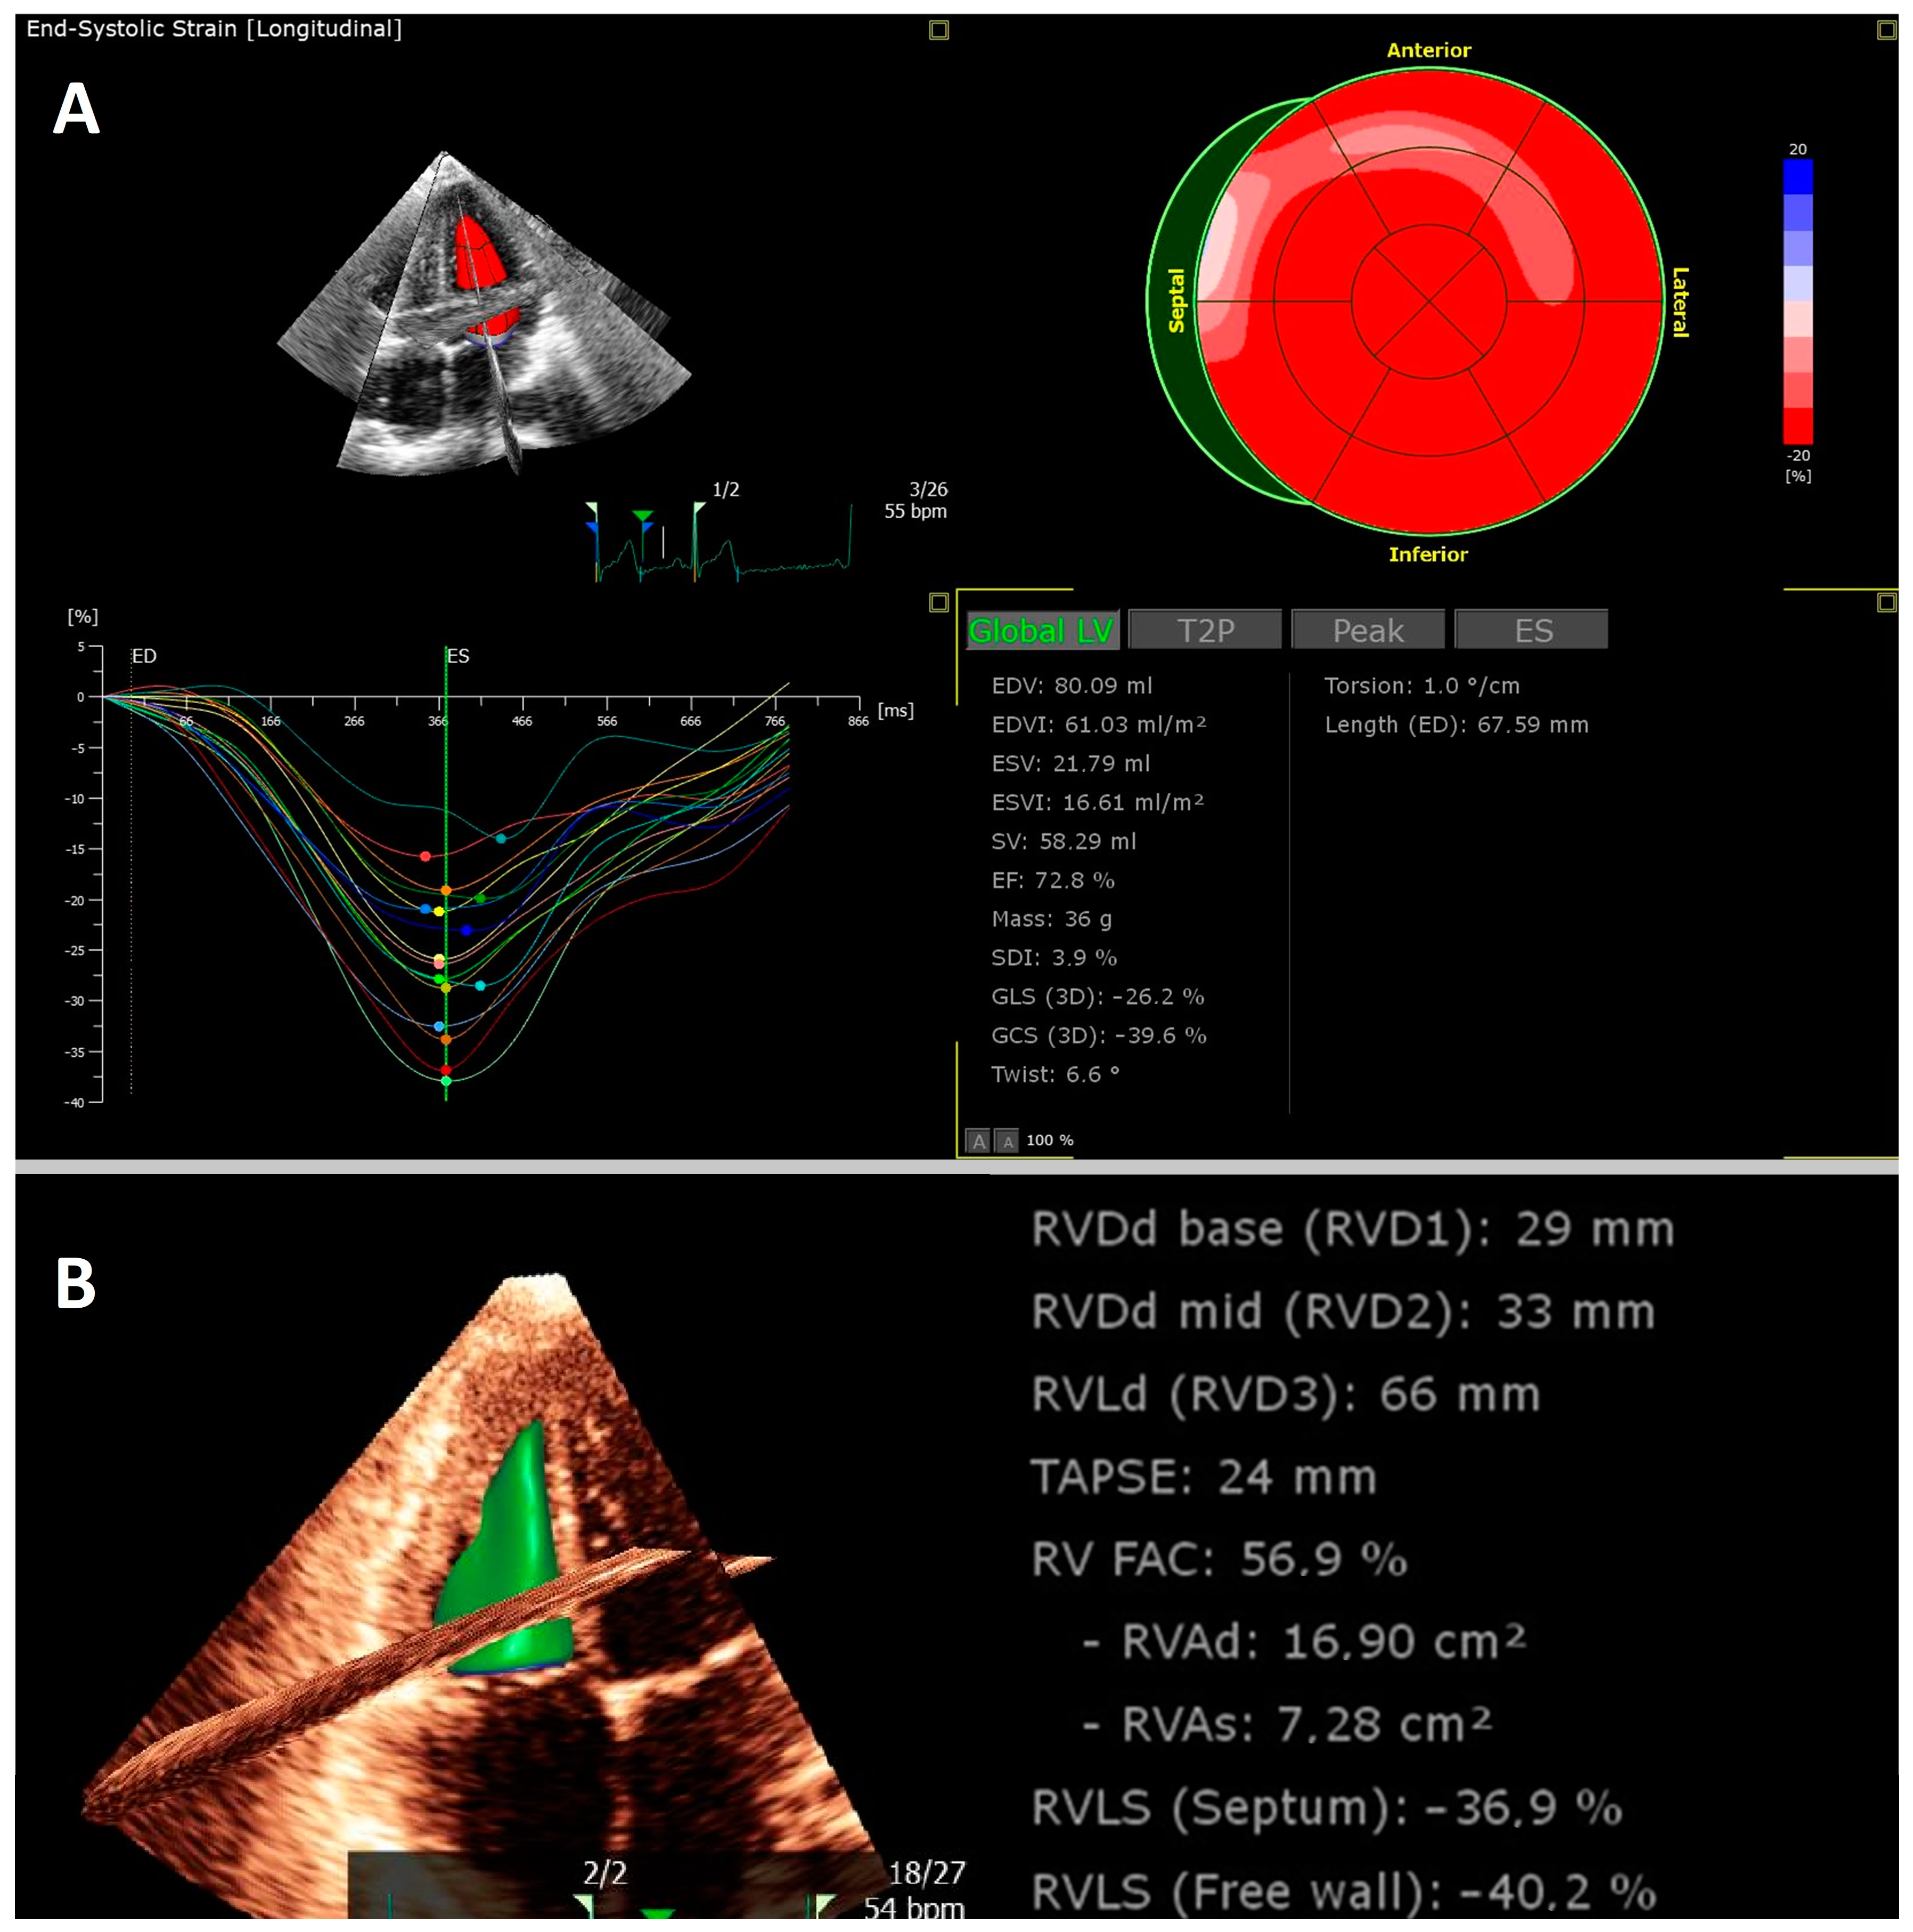

- Schellenberg, J.; Ahathaller, M.; Matits, L.; Kirsten, J.; Kersten, J.; Steinacker, J. Left ventricular global longitudinal strain as a parameter of mild myocardial dysfunction in athletes after COVID-19. Preprint. medRxiv 2023. [Google Scholar] [CrossRef]

- Kersten, J.; Hoyo, L.; Wolf, A.; Hüll, E.; Nunn, S.; Tadic, M.; Scharnbeck, D.; Rottbauer, W.; Buckert, D. Cardiopulmonary Exercise Testing Distinguishes between Post-COVID-19 as a Dysfunctional Syndrome and Organ Pathologies. Int. J. Environ. Res. Public Health 2022, 19, 11421. [Google Scholar] [CrossRef]